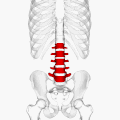

![]() Position of human lumbar vertebrae (shown in red). It consists of 5 bones, from the top down, L1, L2, L3, L4 and L5. | |

In human anatomy, the five vertebrae are between the rib cage and the pelvis. They are the largest segments of the vertebral column and are characterized by the absence of the foramen transversarium within the transverse process (since it is only found in the cervical region) and by the absence of facets on the sides of the body (as found only in the thoracic region). They are designated L1 to L5, starting at the top. The lumbar vertebrae help support the weight of the body, and permit movement.